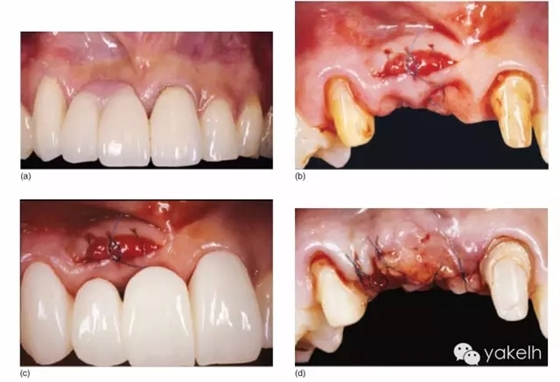

¤¤此項手術的目的是通過多階段的埋入式結締組織移植方式,結合隧道瓣和牙槽嵴軟組織增量的方法,從而解決牙齦退縮問題。而牙齦退縮可能伴有/不伴有鄰近牙槽嵴垂直向和水平向的形態(tài)缺損(圖5.12a~g)。

圖5.12 (a)右上尖牙到左上中切牙固定橋修復,橋體的根方帶粉紅色牙齦飾瓷。(b)根方隧道內(nèi)進行結締組織移植,牙槽嵴軟組織向冠方復位。(c)首次手術完成后戴入新的改良臨時橋。(d)牙槽嵴頂埋入結締組織移植瓣。(e)使用臨時橋,減少手術次數(shù),對橋體位點進行成形,并形成新的牙齦乳頭。(f)最終全瓷修復體的根面觀。(g)新的4單位全瓷固定橋,帶兩個突起式橋體,具有良好的紅色美學和白色美學效果。